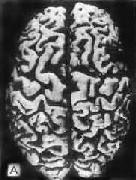

肉眼观,脑萎缩明显,脑回窄、脑沟宽,病变以额叶顶叶颞叶最显着(图16-32),脑切面可见代偿脑室扩张

初老期痴呆的脑 A

初老期痴呆的脑 B

图16-32 初老期痴呆的脑

示脑明显萎缩(A),与正常脑(B)的对比